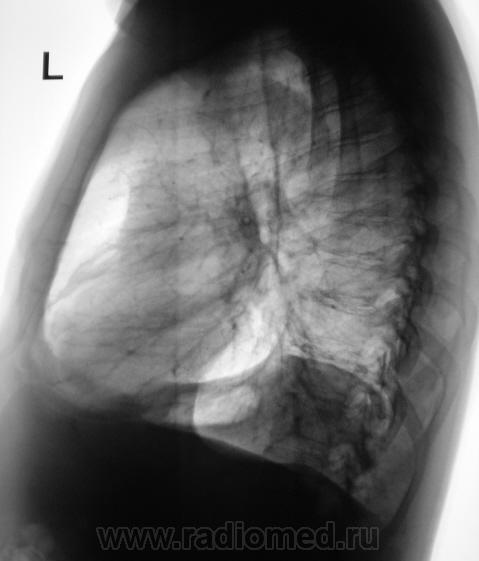

Легкие без очаговых и инфильтративных изменений, увеличены в объеме и прозрачности (эмфизема). Особенно увеличен объем язычковых сегментов левого легкого, несколько уменьшена в объеме нижняя доля. Левый купол диафрагмы расположен несколько выше нормы, особенно задние отделы, плевро-диафрагмальная спайка, увеличено расстояние до газового пузыря желудка. Предварительное заключение: подозрение на нарушение бронхиальной проходимости в левом легком, базальный гидроторакс слева. Дообследование: линейная томография (боковая проекция обязательна, может быть очень информативной), латерография для исключения/подтверждения свободной жидкости в левой плевральной полости.

Легкие без видимых очаговых и инфильтративных измнений. По прямой рентгенограмме левая половина диафрагмы расположена выше обычного. Прозрачность левого легочного поля выше правого. При изучении левой боковой рентгенограммы нижняя доля левого легкого резко уменьшена в объеме в пределах анатомических границ. Затенение базальных отделов левого легочного поля на фоне которого не дифференцируется левая половина диафрагмы. Викарная эмфизема верхней доли левого легкого.

Заключение(вывод): больше данных за ателектаз нижней доли левого легкого (гиповентиляция). Необходимо дополнительное исследование проходимости бронхиального дерева левого легкого. Бронхоскопия, ТМГ, КТ.

Ателектаз нижней доли левого л1гкого.

Что-то на ателектаз не похоже. Какие-то плевральные штучки.